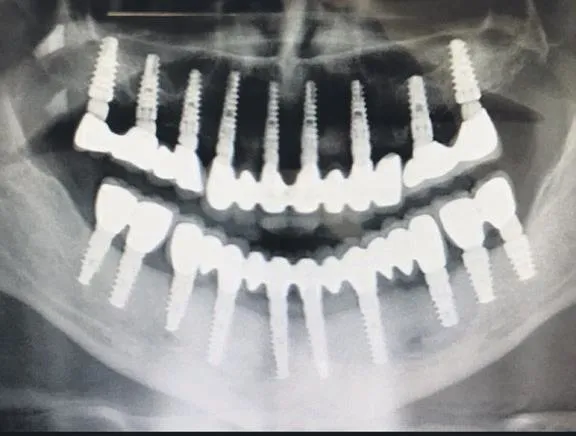

Artık dünya çapında uygulanmakta olan All On Four ve Columbus Bridge yöntemleri lazer destekli uygulandıklarında, açıkta yara yeri olmadığından daha çabuk iyileşmekte ve dikiş de olmadığından gıda birikimini önleyerek ameliyat sonrası diş kullanımını kolay hale getirmektedir.

NAVİGASYONLU İMPLANT

İYI bir diş protezi sadece estetiği değil, hayat kalitesini de artırır. Geleneksel protezler sıklıkla hastalığa sebebiyet verir, acı veren basınç noktaları oluşturur ve tak alma duyusunu azaltabilir. Bu yüzden diş implantları, tek bir dişi ve birçok kayıp dişin yerine veya protezleri yerlerine sabitlemek için kullanılıyor. Gelişmelere rağmen bunu yapmak için gereken ameliyat çok sayıda risk içerir. Örnek olarak, implantlar çoğunlukla estetik olarak olması gereken yere değil, yeterli kemik olan yere konur. 3 boyutlu görüntüleme teknolojisine rağmen implant uygulaması alt çene bölgesi için sınırlıdır. Bu kesin olmayan ve uygun yerde olmayan detaysız delmeye, bu durum da durum yavaş ve yetersiz iyileşmeye sebep olur.

KOMPLIKASYONLARI AZALTIR

Navigasyon sistemi, diş hekiminin protetik ve anatomik planlamasını uygulamaya kesin güvenilirlikle aktarmasını sağlar. Öngörüler ve problemler kaydedilir ve analiz edilir, böylece ameliyat sırasında ortaya çıkmaları engellenir. Uygun tedavi; yüksek kalite standardına, minimal cerrahi yaklaşımla uygun ve güvenilir şekilde ulaşılmasını sağlar. Öncelikle implant yuvasının uygun şekilde hazırlanması ve ameliyat komplikasyonlarının azaltılmasını ve implantın kemiğe kaynamasını hızlandırır. Bu sebeplerden ötürü, hastalar arasında navigasyonlu implant teknolojisi yüksek kabul görür.